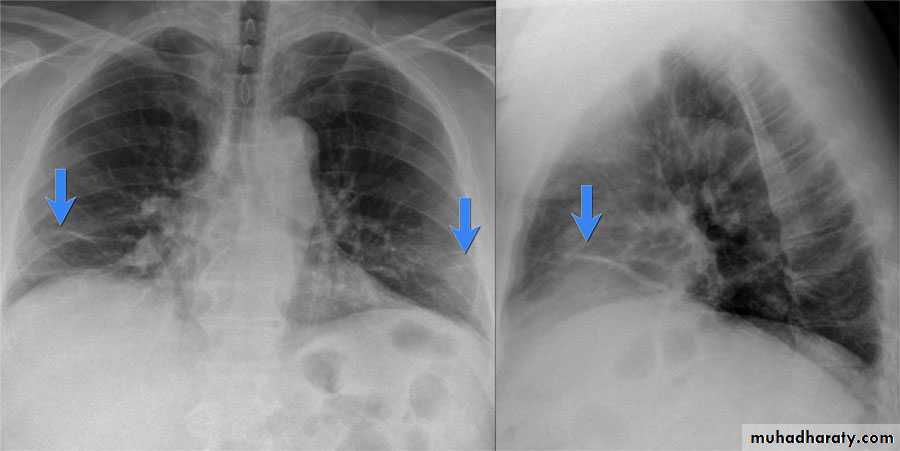

(Collapse) (Massive plural effusion)